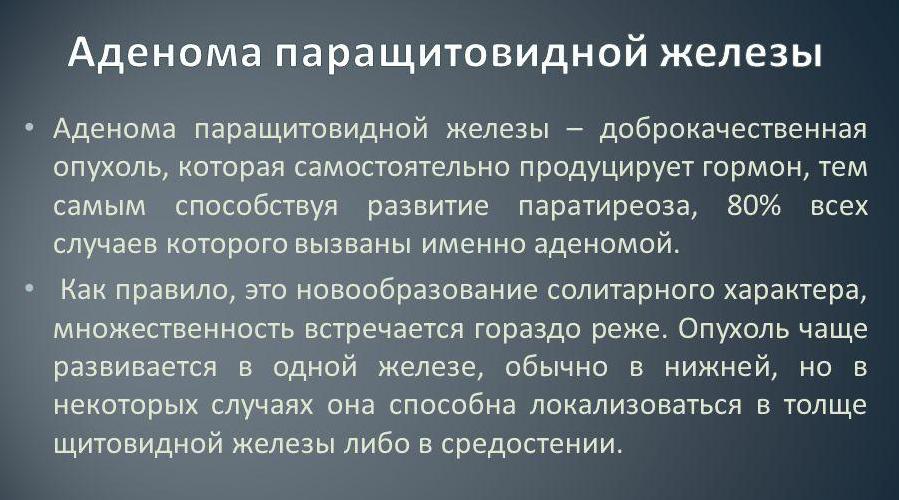

Иллюстрации и схемы по остеопорозу и паращитовидной железе